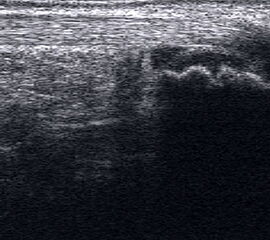

Echogene Verdickung im Subkutangewebe bei Lymphödem

Abbildung 8

Lagerung: Rückenlage.

Schnittebene: Ventraler LS über dem OSG.

Referenzstrukturen: Distale Tibia und Talusrolle, darüber Gelenkkapsel. Befunde: Echogene Verdickung subkutan (Abb. 8), hier peronäal oberhalb des OSG. Bei Varicosis sind in der Subkutis erweiterte Venenkomplexe mit echoarmem Lumen und positivem Doppler-Signal zu sehen.